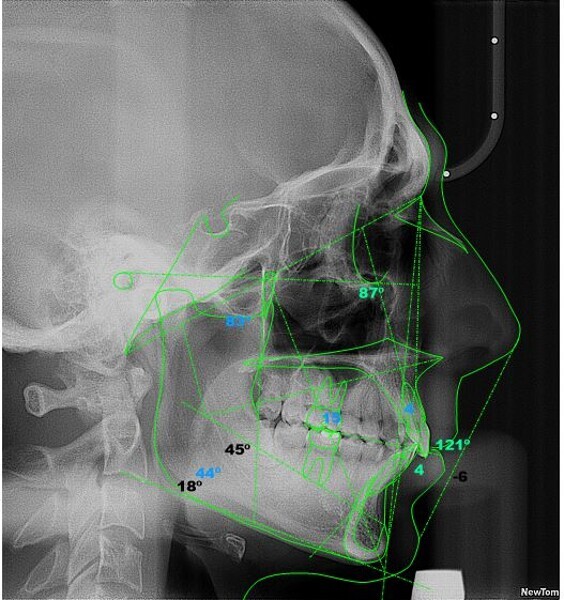

In the radiographic analysis, the dental panoramic tomogram revealed that the two mandibular third molars were unerupted and horizontalised in the mandible. Nothing else relevant was observed in the radiograph (Fig. 3). A cephalometric radiograph was used to perform the cephalometric analysis according to Steiner,6 Ricketts7, 8 and McNamara9 (NemoCeph Studio, Nemotec Fig. 4).

In the Steiner analysis, the SNB angle of 74° suggested mandibular retrusion. Likewise, the ANB angle of 7° indicated Class II, which was also confirmed by Wits analysis (8.3 mm). The results indicated a protrusion of the maxillary incisors and a decreased inter-incisal angle of 118°, which suggested protrusion of the maxillary and mandibular incisors (Fig. 5).

In the Ricketts analysis, a dolichofacial pattern, that is, a facial axis of 84°, was diagnosed. The analysis also confirmed the protrusion of the incisors (Fig. 6).

The McNamara analysis revealed that the size of the mandible that would correspond to the dimensions of the maxilla (91.0 mm) would be between 114.0 mm and 117.0 mm and not the current size of 111.9 mm,9 indicating that the mandible was smaller than it should have been. However, the maxillomandibular difference was 20.9 mm, indicating a Class II skeletal pattern (Fig. 7). From the aforementioned information, we determined a Class II skeletal pattern and dental relationship with retrusion of the lower jaw and an increased overjet and overbite.